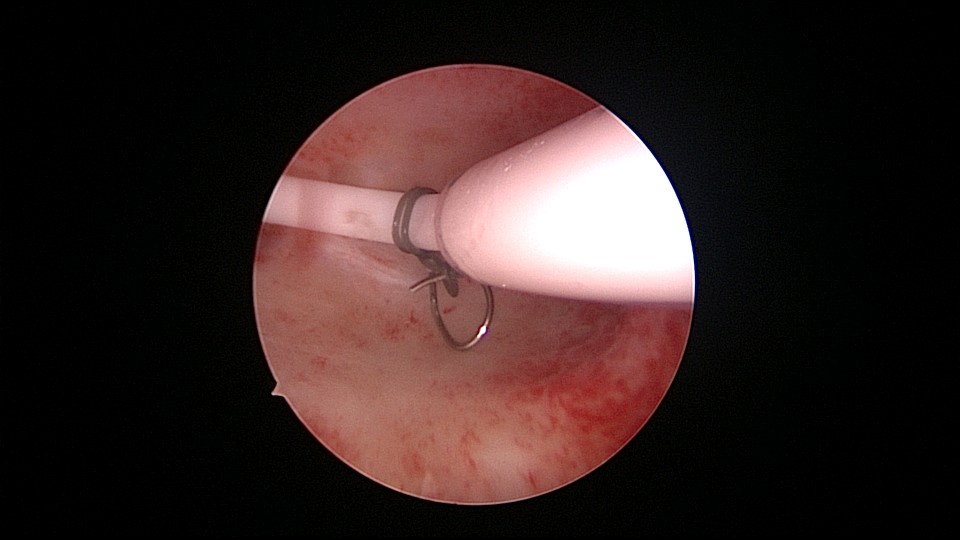

患者53岁,G3P1,顺产1次(产后大出血)。1年前因盆腔器官脱垂行阴道前后壁修补手术,同时行宫腔镜息肉切除手术,病检为增生反应子宫内膜伴出血。2025年2月,绝经2年,阴道出血半天,行宫腔镜检查及诊刮,放置曼月乐并固定,用曼月乐尾丝连接环与不锈钢挂钩,将挂钩插入宫底肌层固定,异物钳原位固定曼月乐,退出宫腔镜,结束手术。2025年4月复查B超曼月乐位置正常,环顶端距宫底1.1cm。病检为子宫内膜增生,不伴非典型增生。